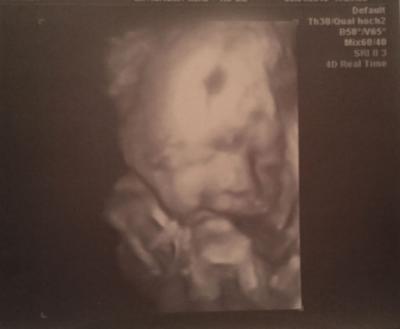

Und das war sooo toll. Unser kleine Mann und das ist mehr als 100% eindeutig ein Junge, ist sooo gelenkig. Er hat nach ein paar Bildern ständig den Fuß im Gesicht gehabt. Außerdem fand unsere FA, dass er eine sehr starke Mimik hat. Er hat ne Schnute geschnitte, dann gelacht, dann gegähnt, dann sozusagen geredet und dann wieder so getan als wenn er singen würde ^^ war voll lustig. und er ist sooo süß Wir haben auf jeden fall gesheen, dass er total glücklich und freudig ist. er grinst ganz oft :-D Übrigens wurde nochmal vermessen. Größe haben wir jetzt nicht erfahren..ist irgendwie unter gegangen, aber er wiegt etwa 700g und laut dem berechnen stand da ET 12.05. und mein eigentlicher ET ist 22.05. Na mal sehen. also ändern tun wir das nun erstmal nicht mit dem 22.05. hab aber eh schon im gefühl, dass er früher kommen wird. Jetzt spann ich euch nicht mehr so auf die Folter. Ich hab ganz viele Bilder und hab euch mal die 4 schönsten raus gesucht. Und die kommen jetzt :-)

Bild zu Zurück vom 3D US :-D - Forum für Mai - Mamis